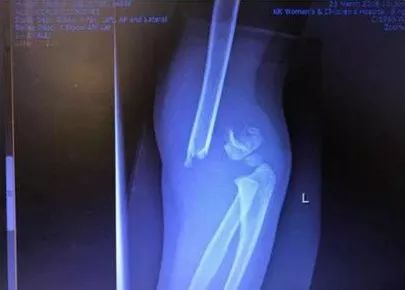

▲女孩骨折的手臂需要用两根铁丝固定骨头

在竹脚妇幼医院,女孩拍了X光,从X图上可以看出,女孩应该是手肘骨折了。